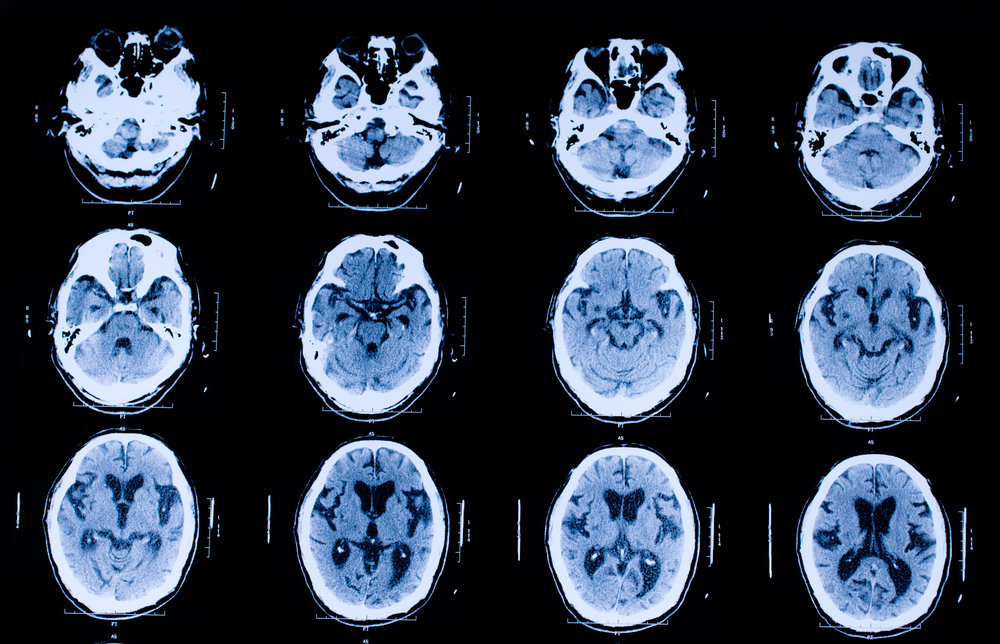

Computed Tomography Scan

(CT Scan)

- More powerful ionizing radiation than X-ray

Takes a 360-degree image of internal organs, spine, and vertebrae

- Gives pictures in cross-sections

- More detailed look at organs, soft tissue, blood vessels

- Better diagnostic for cancer, heart disease, infection

- More expensive than X-ray